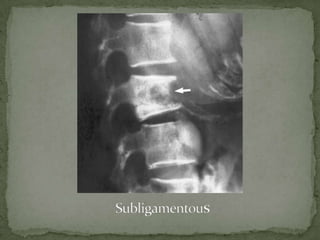

Anterior Subperiosteal –

 begins at the anterior vertebral margin underneath the

periosteum

 spreads beneath the ALL

 subtle anterior erosions of multiple vertebrae

 clinical symptoms are severe in relation to the minor

radiographic abnormalities

 Disk destruction maybe late and anterior erosions are

difficult to detect on plain radiographs.